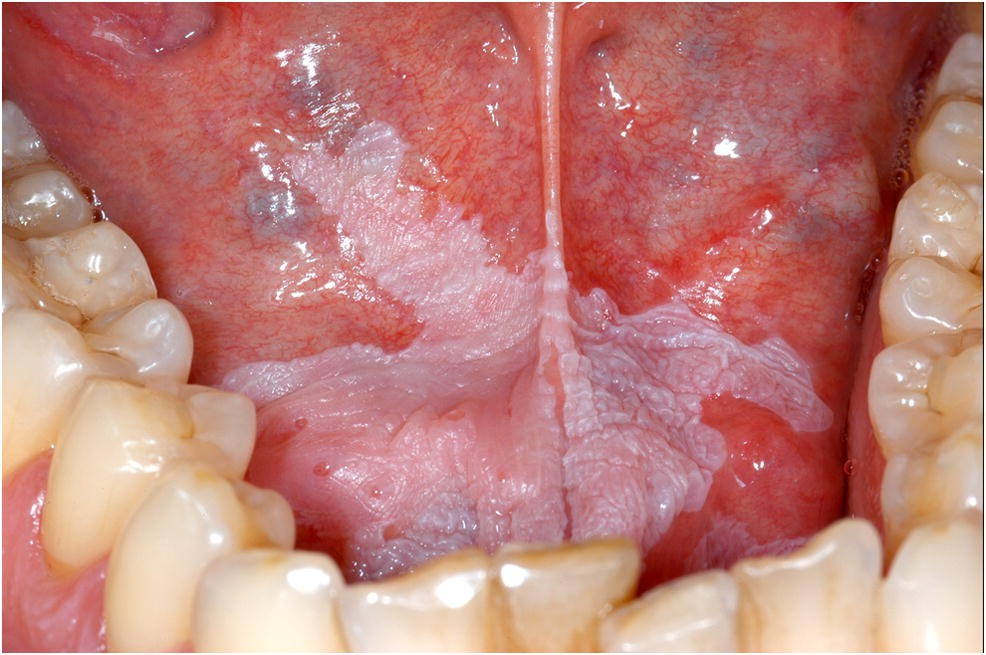

লাইকেন প্ল্যানাস (Oral Lichen Planus)

লাইকেন প্ল্যানাস (Oral Lichen Planus) হলো মুখগহ্বরের একটি দীর্ঘস্থায়ী প্রদাহজনিত রোগ, যা সাধারণত একটি অটোইমিউন কন্ডিশন হিসেবে বিবেচিত হয়। এই রোগে শরীরের ইমিউন সিস্টেম ভুলবশত মুখের টিস্যুর বিরুদ্ধে প্রতিক্রিয়া দেখায় এবং মুখের ভেতরে বিশেষ ধরনের সাদা বা লালচে দাগ তৈরি করে। এটি মুখগহ্বরের মিউকোসাল টিস্যুতে সবচেয়ে বেশি দেখা যায় এবং অনেক সময় ব্যথা, জ্বালাপোড়া ও অস্বস্তির কারণ হয়।Peri-dental Diseases

লাইকেন প্ল্যানাসের লক্ষণ (Symptoms of Oral Lichen Planus)

- মুখের ভেতরে সাদা লেইসের মতো দাগ বা লাইন (Wickham’s Striae)।

- লালচে প্রদাহযুক্ত অংশ বা আলসার।

- জিহ্বা, গালের ভেতরের অংশ, মাড়ি ও ঠোঁটের ভেতরে সবচেয়ে বেশি দেখা যায়।

লাইকেন প্ল্যানাসের ধরণ (Types of Oral Lichen Planus)

- Reticular Type – সাদা জালের মতো দাগ, সাধারণত ব্যথাহীন।

- Erosive Type – লালচে প্রদাহ ও আলসার তৈরি হয়, ব্যথা বেশি হয়।

- Atrophic Type – মিউকোসা পাতলা হয়ে যায় এবং প্রদাহ বাড়ে।

- Plaque-like Type – সমতল সাদা দাগ, অনেকটা লিউকোপ্লাকিয়ার মতো।